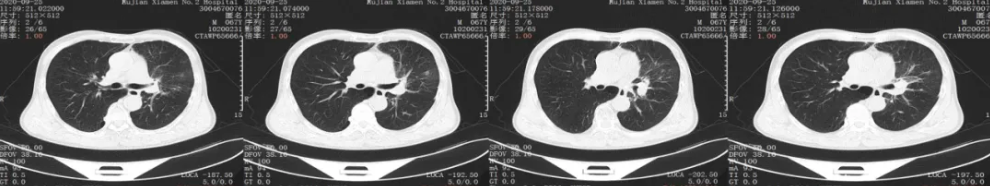

胸部CT平扫+增强:2021年10月复查

胸部CT平扫+增强:用药31个周期后复查

疗效评价:SD

后续治疗:考虑专家推荐免疫治疗2年,目前患者病情稳定,建议停用免疫维持,进行观察

胸部CT平扫+增强:2023年2月17日复查CT

疗效评价:PD(2023年2月17日CT报告提示肿瘤进展)